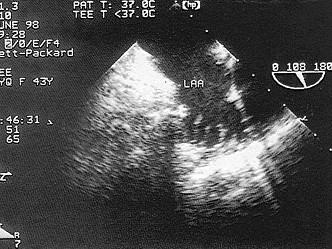

该图箭头显示图像为?(?)A.左心耳B.肺静脉C.右心耳D.上腔静脉E.下腔静脉

问题 该图箭头显示图像为?(?)

选项 A.左心耳 B.肺静脉 C.右心耳 D.上腔静脉 E.下腔静脉

答案 A